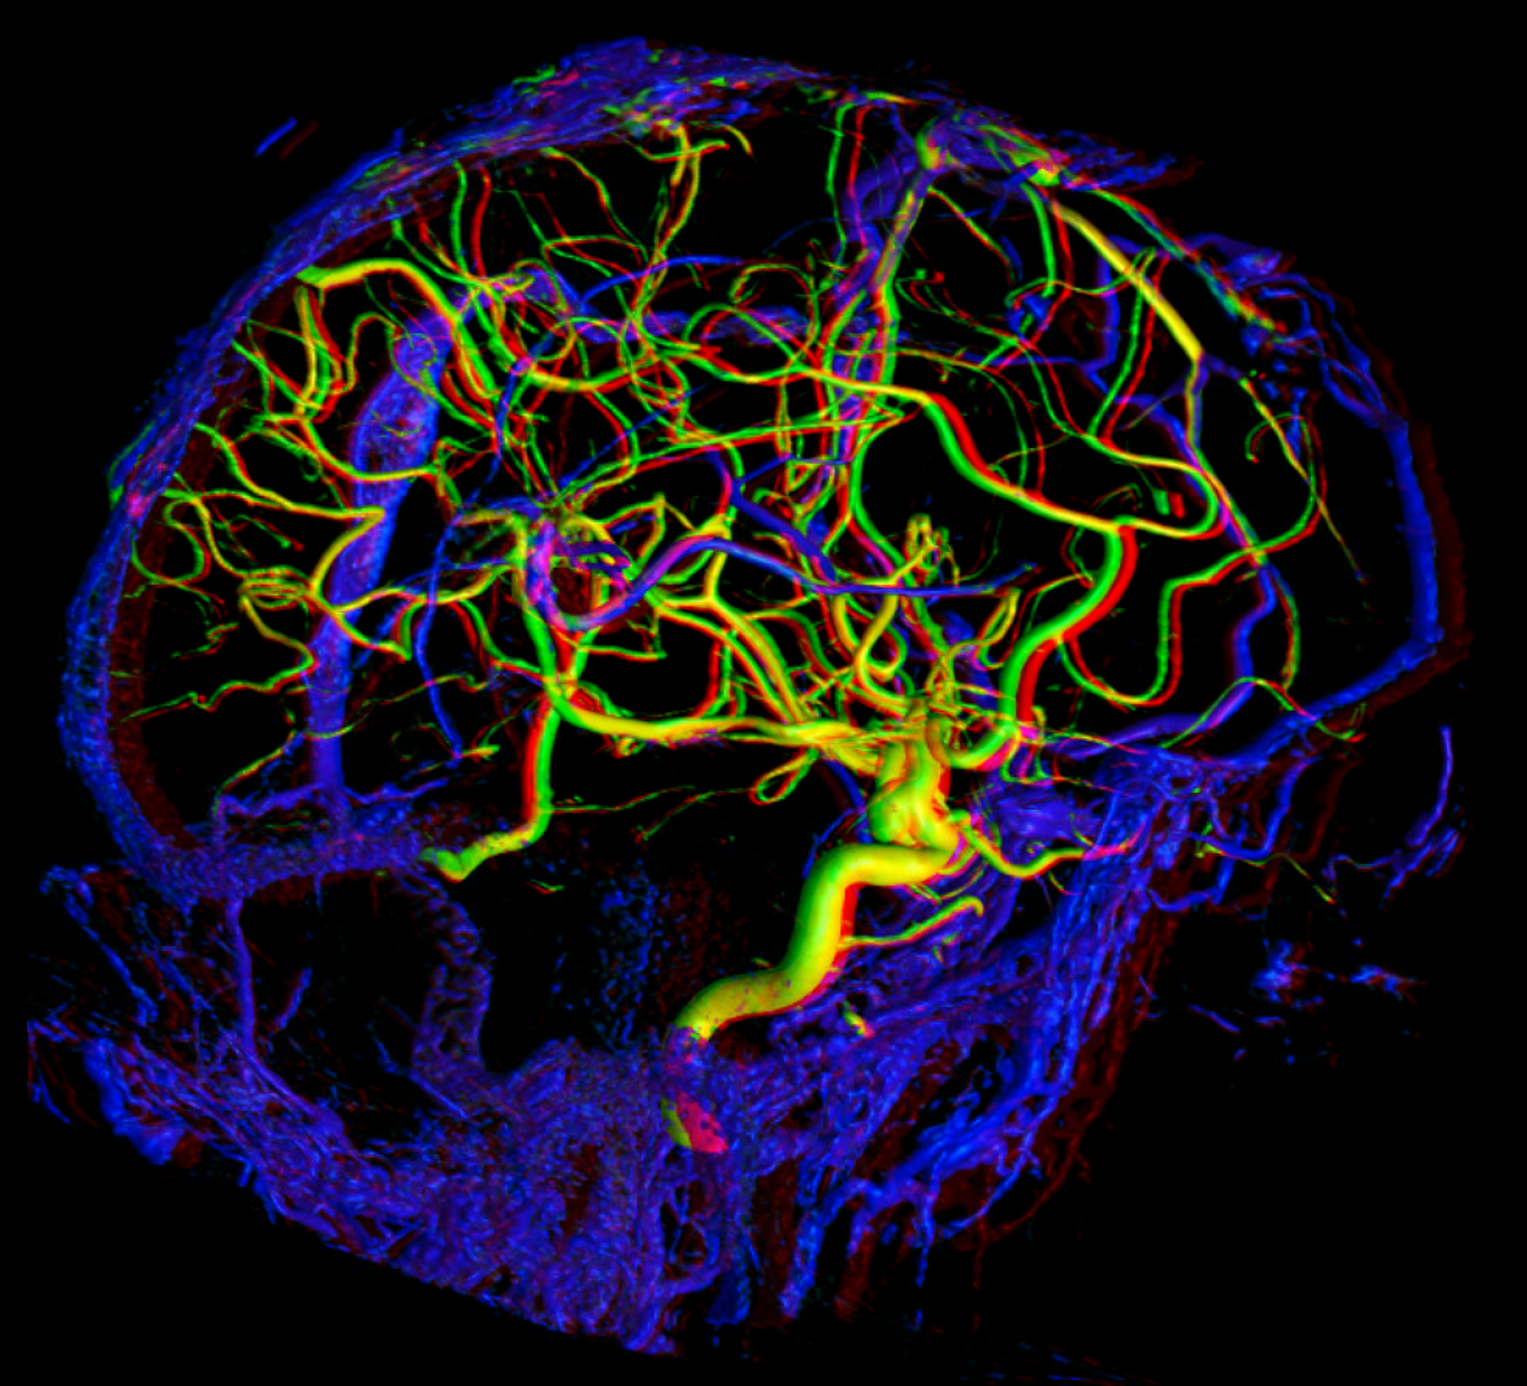

Below are some volumetric images, before we dive in

Pause movies to scroll thru individual frames